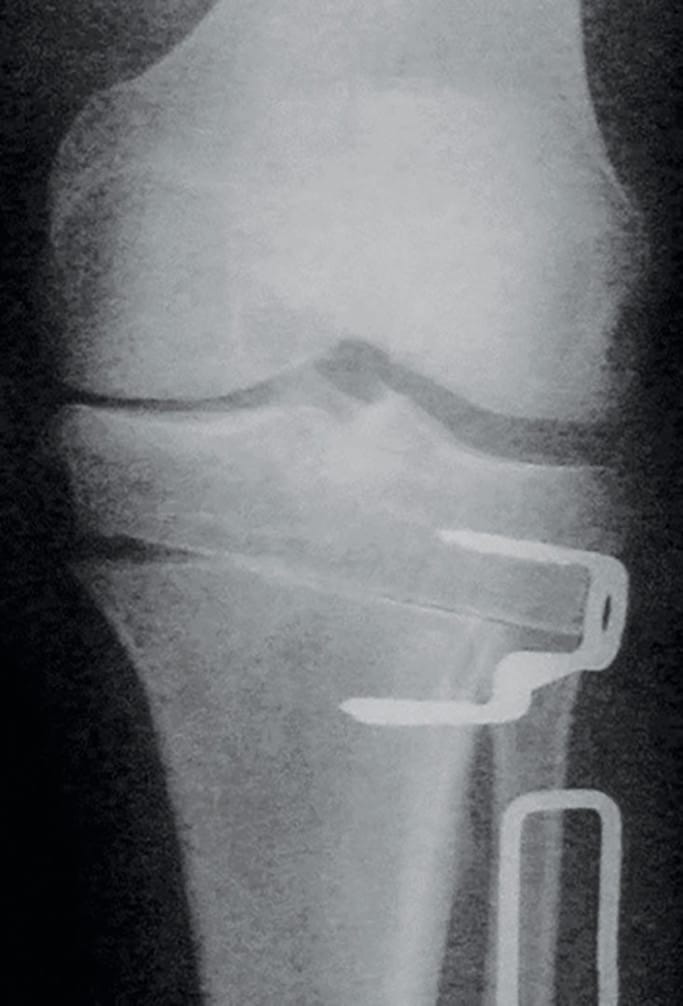

The wedge is removed and the metaphysis is allowed to close with gentle valgus force (Figure 4). A single metallic Krakow staple (Smith & Nephew, Memphis, Tennessee) applied (Figure 5).

In patients who have more than 3mm of MCL laxity with valgus stress (pseudolaxity), we make two modifications to the technique to restore tension to the MCL (Figure 6). Firstly, the initial osteotomy is completed through the medial cortex, releasing cortical and periosteal constraints but leaving the MCL intact. Secondly, the apex of the second, distal osteotomy is aimed short of the medial cortex (only two-thirds of the transverse width across the tibia). When the leg is now forced into valgus, the effect is a simultaneous closing wedge lateral osteotomy, and an opening wedge medial osteotomy. The mechanical axis is still shifted laterally, and the tension in the medial collateral ligament is restored. No graft is necessary as the medial wedge is small (Figure 7).